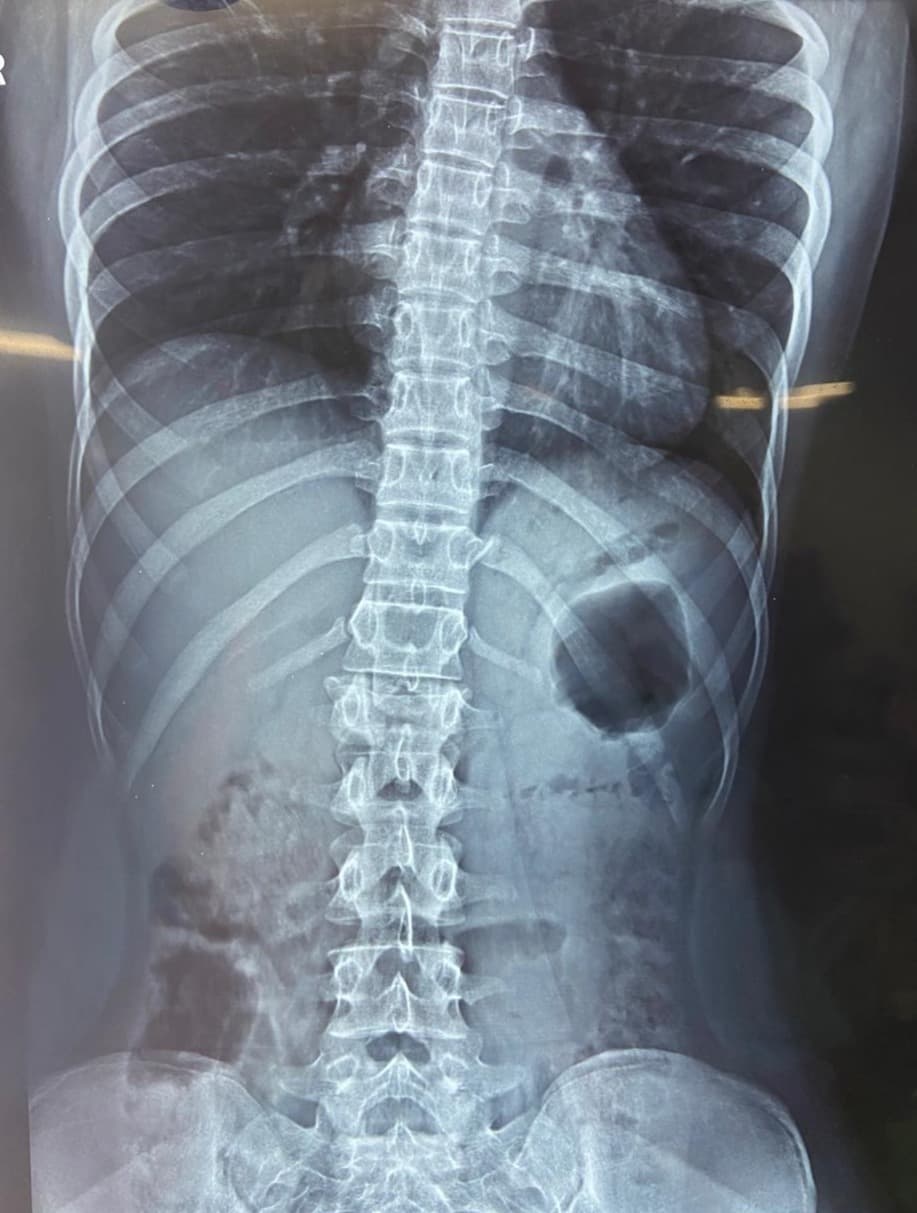

A 17-year-old girl was brought to us after a fall from the first floor of her house. She had sustained a severe injury to her spine and was unable to walk at the time of admission. X-rays and MRI revealed an L1 burst fracture with compression over the spinal cord. On clinical examination, she had paraparesis—weakness of both lower limbs—with significant difficulty in standing and moving. The family was deeply worried as her ability to walk again was uncertain. Given the severity of the spinal cord compression and the risk of permanent neurological loss, she was taken up for emergency posterior stabilization and decompression of the spinal cord